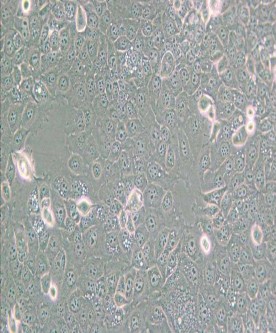

KYSE-30人食管鱗癌細胞

中文名稱 :人食管鱗癌細胞

細胞簡稱 :K YSE-30

細胞形態 :上皮細胞樣,帶有長的偽足

生長特性 :貼壁細胞

D erived from welldifferen tiatedin vasive esophagealsquam ouscellcarcinom a resected from middlein tra-th o racic esophaguso fa 64-year-old Japanesem an priorto treatm ent;cellline Established from tum orcells h etero tran splan tedinto athymicmice;d escribedin theliterature to be heterotransplan tablein athymicmiceand to carry p53 m utationandam plification ofcERB B,M YC and CYCLIN D1

倍增時間 :~ 20-30 hours

供體年齡 :女;64歲

組織來源 :食管鱗狀上皮

細胞類型 :腫瘤細胞

腫瘤類型 :食管癌細胞